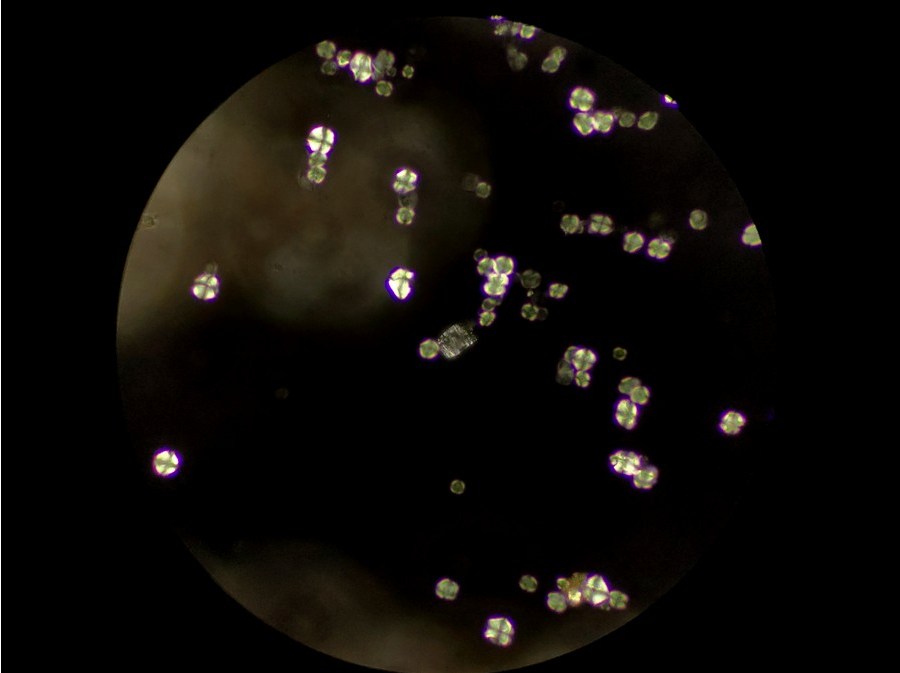

明場鏡檢下的中藥顆粒

使用生物顯微鏡ML31進行明場鏡檢,可見很多顆粒,少量雜質,可能是殘留的草藥植物纖維,也可能是玻片或者水本身帶的雜質。

高倍明場鏡檢

使用高倍率的物鏡,可以更清晰地看到顆粒的形狀,但看不出植物草本結構,另外背景發現了更多雜質。